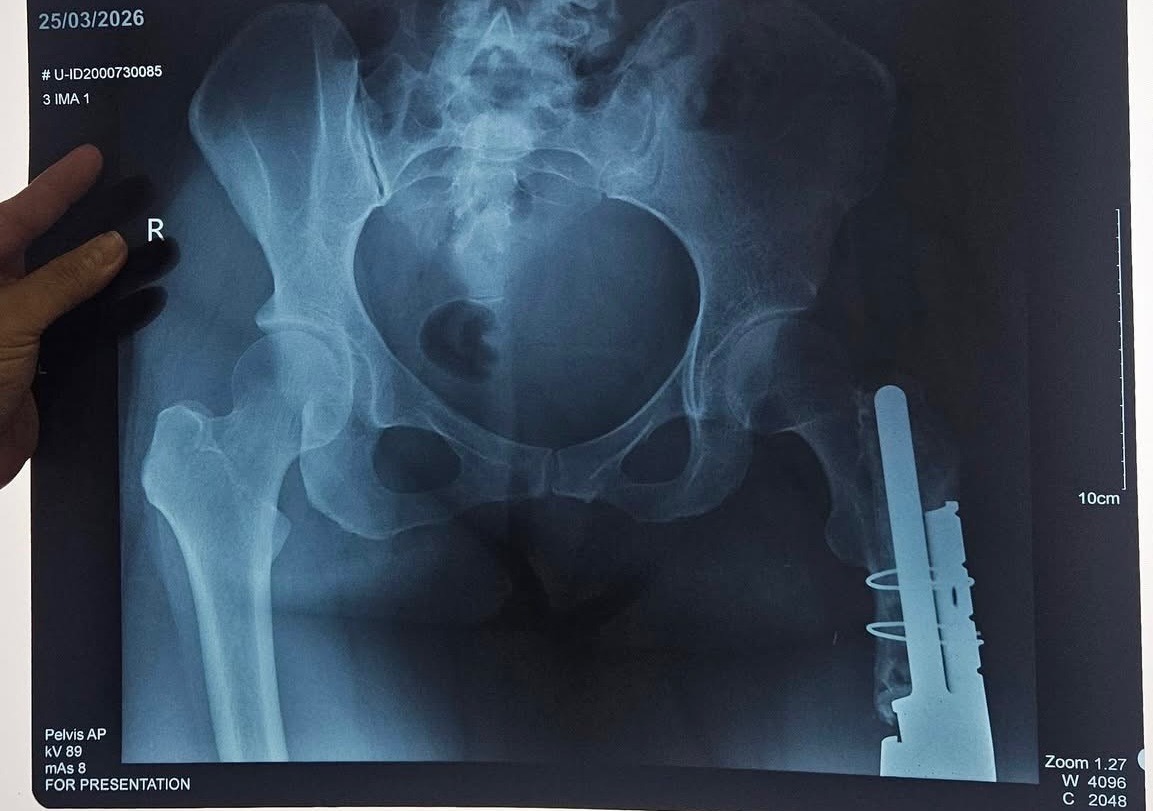

Unfortunately, another hurdle in life has presented itself before her. Her prosthesis has broke internally resulting her inability to move her leg at all and is extremely painful. She is currently waiting to hear from her doctor who is tirelessly looking for a replacement of the screw that had broken off. It has been decades since the prosthesis was surgically placed, chances of finding the part is slim. Surgery to replace the screw is costly… but if they are unable to find the exact replacement then they will need to replace the whole entire prosthesis, which is unimaginably more expensive… Michelle and her mother are trying their best to ask the Filipino government for help and is jumping through hoops to obtain any financial support. But as you can guess, it can be lengthy and straining. I fear that the longer she waits, the higher chance of her encountering complications, especially circulation issues, will put her limb at risk.

In the middle of her meeting, Mich suddenly had to be rushed to the hospital. After consultation and x-ray, we found out that na nabali yung leg prosthesis niya. Hindi na po niya maramdaman ung lower leg niya, and because of this, Mich currently cannot walk or put weight on her left leg. For now, she is confined to the bed and can only move using crutches or a wheelchair as advised by her doctors.

We’ve been advised that her prosthesis now needs to be fully replaced. It needs to be ordered and imported which will take time. Wala pa pong exact amount na masabi ang doctors dahil customized pa ito kay Mich, but we are trusting God as we begin to prayerfully prepare and pag-ipunan ang kanyang replacement.